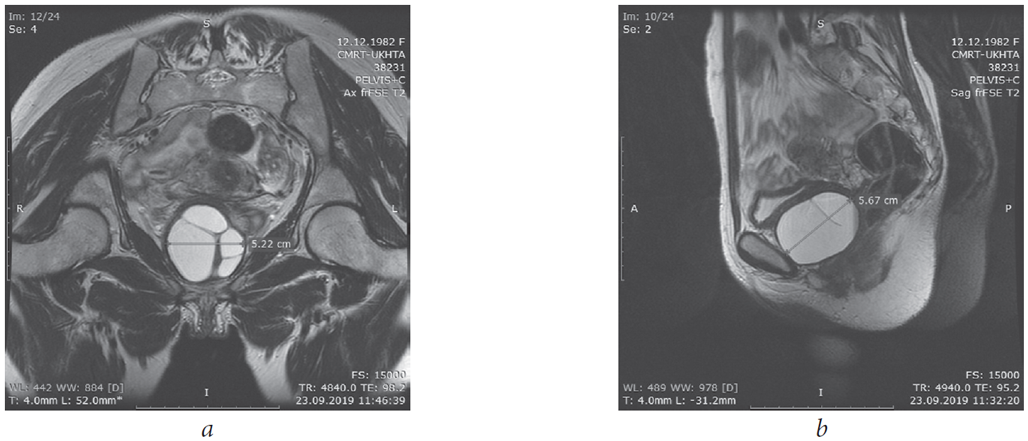

Surgery course. An incision was made along the anterior wall of the vagina after hydropreparation (Fig. 2). A paraurethral cyst with a diameter of about 6 cm was bluntly and sharply separated (Fig. 3). Its walls were excised (Fig. 4). The bladder was filled up to 250 cm; there was no urine leakage into the wound. The cyst bed (Fig. 5) was sutured with interrupted sutures (Vicryl 3–0). A Bülau drain was installed in the wound to the cyst bed, the incision of the vagina was sutured, and hemostasis was performed. A tampon was placed in the vagina. The urinary bladder was drained with a Foley catheter 18 Ch.

Fig. 3.Exposure of the paraurethral cyst walls

Fig. 4.Exposure of the paraurethral cyst walls

Fig. 5.Paraurethral cyst’ bed